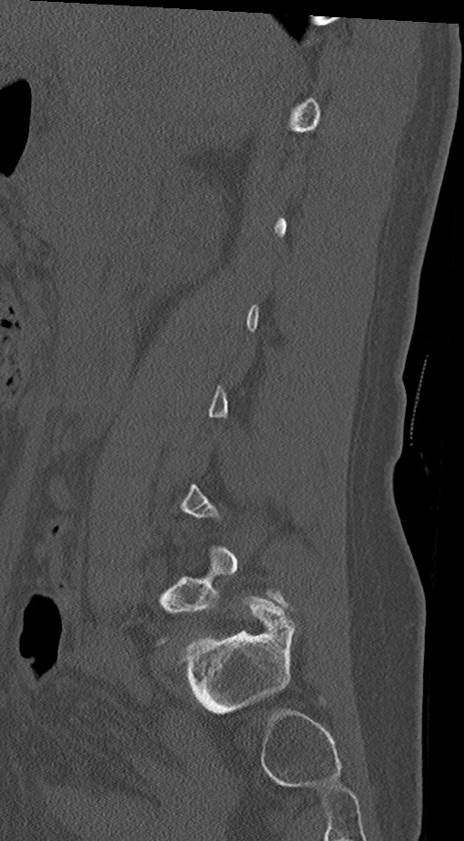

腰椎CT

冠状断像